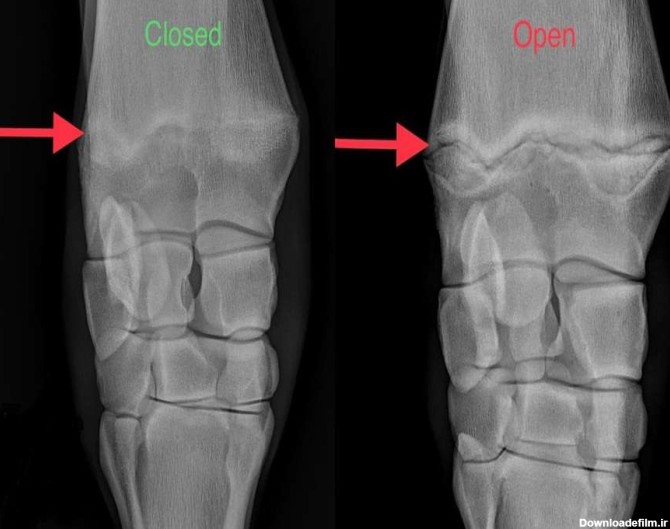

صفحه رشد، محل رشد استخوان جدید در کودکان هست.که این صفحات در دختران در سن 15 و پسران در سن 17 سالگی بسته میشوند اما استثنا نیز وجود دارد...

صفحه رشد چه کاری انجام می دهد؟ - علائم بسته شدن صفحه رشد - علائم صفحه رشد بسته - افزایش قد بعد از بسته شدن صفحات رشد چجوری ممکن است؟ + عکس صفحه رشد باز و بسته